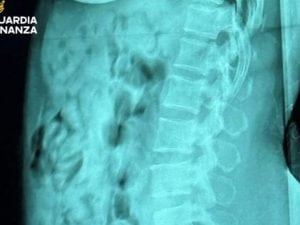

I funzionari dell'Agenzia delle Dogane e Monopoli (Adm) e i militari della guardia di finanza all'aeroporto Orio al Serio di Bergamo hanno arrestato una 46enne trovata con 120 ovuli di eroina nello stomaco. La donna era appena arrivata con un volo da Bruxelles.